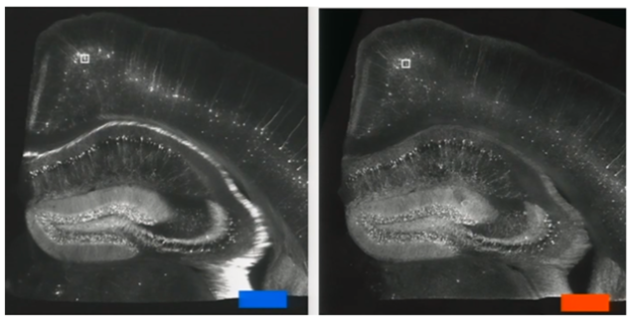

Up until now, most microscopy has operated on a pretty simple principle: Use tricks of light to make small things appear big. A group of MIT scientists, however, are trying something radically different. They've developed a technique that physically makes tiny neurons bigger, and yes, it uses a chemical commonly found in diapers.